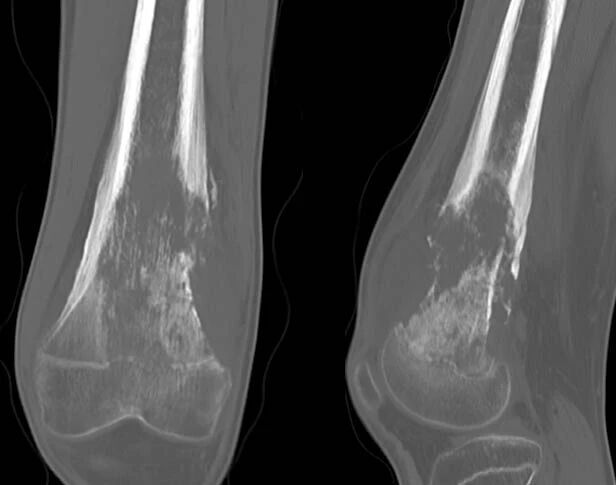

瘤软骨钙化

瘤软骨常表现为环状钙化, 是诊断软骨类肿瘤较为可靠的影像学征象。环状钙化形成于环状软骨、以及软骨小叶边缘的软骨基质。钙质沉着可呈小点状、小条状、半环状或弧形;亦可浓密相连、重叠呈菜花状。钙化环的形态和密度可反映瘤组织分化程度, 通过观察钙化环的形态和密度,有助于良恶肿瘤的鉴别。良性瘤软骨之瘤细胞分化好、生长缓慢、血供充分, 钙化环完整,密度高, 边缘清楚。良性软骨类肿瘤如骨软骨瘤(图 35)、软骨母细胞瘤(图 36)、内生软骨瘤(图 37)等均可于瘤组织内发生环形钙化。恶性瘤软骨则呈密度淡薄, 边缘模糊的不规则钙化,恶性骨肿瘤的环形钙化,最多见于软骨肉瘤(图 38),其次是骨肉瘤。CT 是发现肿瘤内软骨钙化最为敏感的检查方法。

图 38.瘤软骨钙化:软骨肉瘤